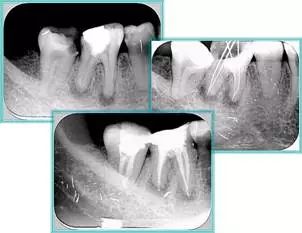

6. 术后 X 线片

术后 X 线片用来评定根管充填 长度、致密度(管壁清晰、侧枝)等指标。

牙胶尖什么颜色​牙齿“晓”“技”|最全根管治疗的标准步骤,以及细节把握_https://www.jmylbn.com_新闻资讯_第16张

左图为根管充填术后 X 线片。图中可见,根管充填较好。右下图有白色小点,为侧方加压导致糊剂挤出所致,表明根管充填比较致密。

致密、恰到好处的充填可去除干净根管里感染灶,机体逐渐恢复。

牙胶尖什么颜色​牙齿“晓”“技”|最全根管治疗的标准步骤,以及细节把握_https://www.jmylbn.com_新闻资讯_第17张

多根牙时候需进行偏移投照,正位投照无法说明具体哪根牙根管充填效果。        二、根管预备及充填要求